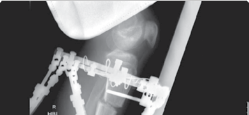

| 43. Monolateral rail (Figure 15.7) 1. If no risk of joint subluxation | |||

| 2. Three half-pins proximal and, at least, three distal to corticotomy | |||

| 44. Circular frame | |||

| 1. If risk of joint subluxation | |||

| 2. Span knee/pelvis | |||

| 3. Arches/two-thirds rings to allow mobility | |||

| 4. Same principles as earlier | |||

| Figure 15.7 Radiograph of femoral limb reconstruction system (LRS) rail. | |||